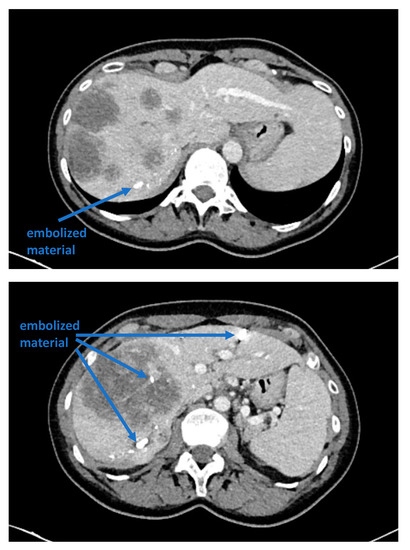

Recent reports have proposed several methods to augment the future liver remnant before extended right resection of the liver [1,2,3,4,5]. Although portal venous embolization is well established and produces satisfactory results in many patients, the growth of segments II and III is often slow and sometimes insufficient in volume (Figure 1 and Figure 2) [6,7]. This precludes many patients from potentially curative resection. The technique of in-situ liver transsection and portal venous division (also referred to as ISLT or ALPPS) and secondary completion hepatectomy, has gained some attention over the past decade to generate faster and more efficient growth of the liver remnant [3,4,5,8]. The technique of this procedure varies. Due to the high complication rate of both procedures, many modifications have been described to minimize the trauma of the first step [9,10,11]. However, a standardized initial operation can be performed safely and reduces the complication rate in the vulnerable phase before the second operation. To obtain optimal growth and to prevent situations that make the completion hepatectomy more urgent, the initial operation has to be designed to avoid bile leaks, venous congestion and segmental liver ischemia. For accurate planning of the two steps of this complex operation, a detailed understanding of the underlying pathology and the anatomy is of major importance. Preoperative imaging will have to identify arterial and venous blood supply and drainage as well as the biliary anatomy. We routinely use computed tomography with a portal and arterial phase. An MRCP is reserved for additional questions regarding the biliary tree. The patient is then presented to and discussed in our multidisciplinary hepatologic tumor board before treatment.

Figure 1. A patient with a multilocular, large hepatocellular carcinoma, a small left lobe that would not suffice to avoid liver insufficiency after resection, and insufficient portal venous embolization.